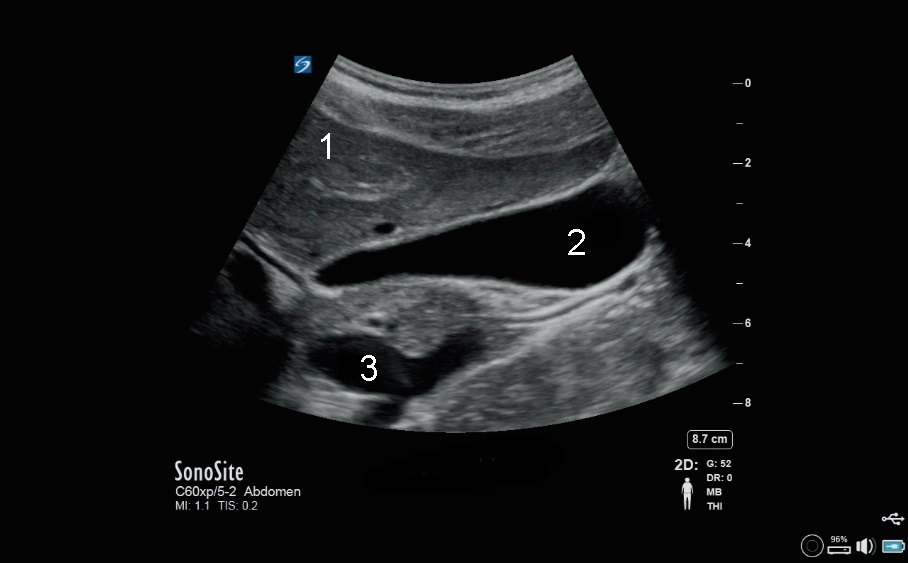

胆嚢 X-Porte画像

肝臓

胆嚢 (GB)

下大静脈(IVC)